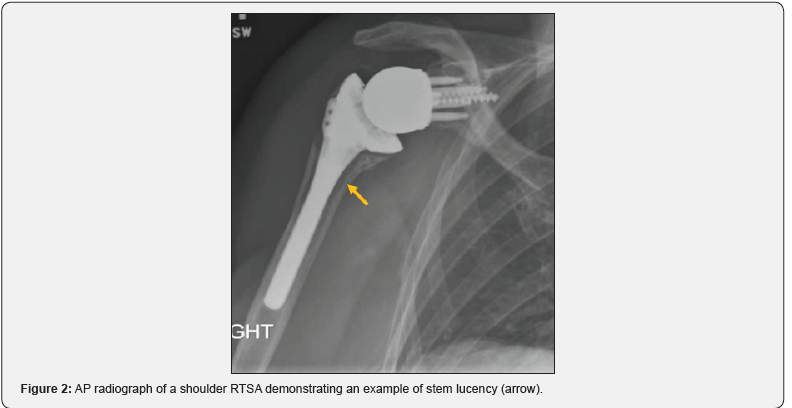

Radiographic analysis of the humeral stem was performed by comparison of immediate post-operative AP radiograph with the latest follow-up imaging available. This analysis was performed by a single examiner to avoid interobserver variability. Radiographic analysis as described by Sanchez-Sotelo, et al was used to evaluate the films for radiolucencies [9,10]. This technique identifies 8 separate zones around the humeral stem with significant lucencies considered to be >2mm (Figure 1). Lucent lines were measured using Synapse’s standard digital measuring tool to within 0.5mm (Figure 2). If lucencies were found in 3 or more zones, the stem was considered “at risk” for clinical loosening [9,10]. We also recorded the presence of subsidence, scapular notching, and endosteal erosion or sclerosis. Subsidence was measured as any change in vertical distance between the superior most margin of the greater tuberosity (or proximal edge of lateral cortex in our fracture scenario) and the superior margin of the implant between images [10]. Scapular notching was classified from 0-4 based on the Sirveaux Classification (Figure 3) [11].

Overall, only 10 of 64 prostheses (15%) had any lucencies at a mean follow up of 12 months. Of these 10 prostheses, 7 were uncemented and 3 were cemented. Radiolucent lines were limited to 1 zone (6 shoulders) and 2 zones (4 shoulders). None of the RTSAs with lucent zones had more than 2 zones of involvement, thus implying that all stems were free from risk of clinical loosening based on the Sanchez-Sotelo technique [12]. The overall mean lucency thickness was found to be 3.4mm (range 2-6mm). The Average thickness was 4.5mm for cemented and 2.8mm for uncemented stems. The 3 most common zones of lucencies in order were zone 2, zone 6, and zone 3 (Table 2).